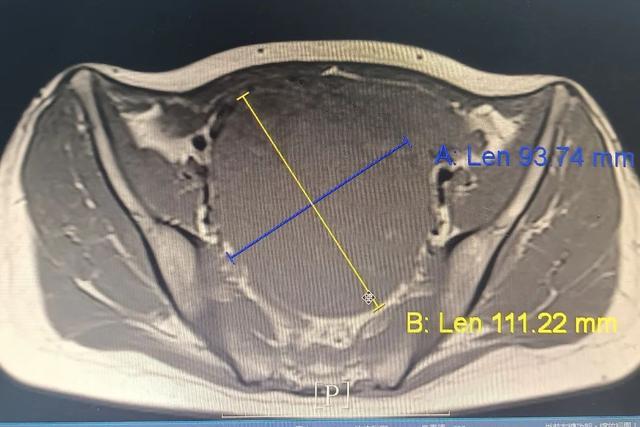

段女士因发现子宫肌瘤3年、尿频3月就诊,完善B超及妇科检查后收住该院妇科,入院完善盆腔核磁检查后确诊为宫颈肌瘤,大小约为11*9*11cm,鉴于患者要求保留子宫且希望进行微创手术,手术团队面临了巨大的挑战。